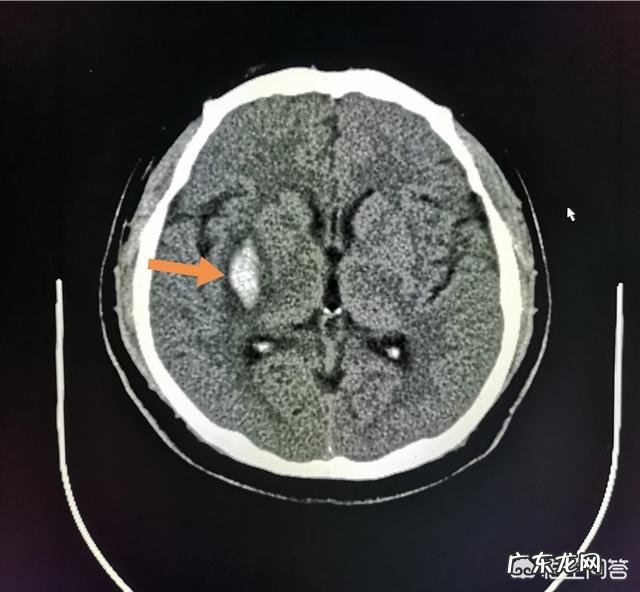

3.男性,37岁,企业职工查出高血压近10年,对西药很抵触,未接受正规zhi疗,酒局稍多,突发头疼一小时 。

脑CT发现右侧基底节脑出血: